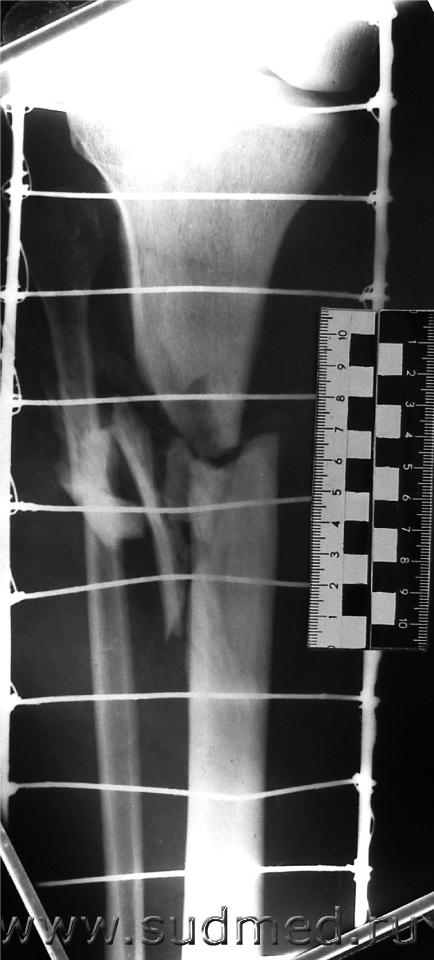

При возможности мы делаем так. Уважаемый Filin может конечно не согласиться и это его право.

Эскизы прикрепленных изображений

Судебная медицина - Прикрепленное изображение Судебная медицина - Прикрепленное изображение Судебная медицина - Прикрепленное изображение Судебная медицина - Прикрепленное изображение Судебная медицина - Прикрепленное изображение

А вот превращать трехмерное изображение в двухмерное (как это сделано Вами со снимком) - вряд ли можно расенить как удачное проведение экспертизы.

Главная проблема в СМ-рентгенологии - установление стороны и поверхности разрушения кости.

С десяток приспособлений придумано для этого ( в основном сетки или металлические стержни, помещаемые рядом с костью) и снимками её минимум в четырех проекциях.

А Вы берете одну (!) проекцию и сходу - реконструкция.